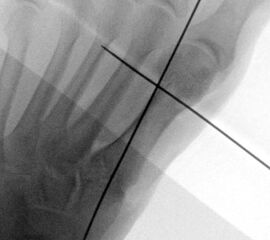

Röntgenaufnahme des Fußes im Stehen im dorsoplantaren und seitlichen Strahlengang (Abb. 1a-b).

Beurteilung des ersten Intermetatarsalwinkels (IMA), des Hallux valgus Winkels (HVA), des distalen (Distal Metatarsal Articular Angle, DMAA) und proximalen Gelenkflächenwinkels der Grundphalanx (Proximal Phalangeal Articular Angle, PPAA).

Abbildung 1a

Abbildung 1b